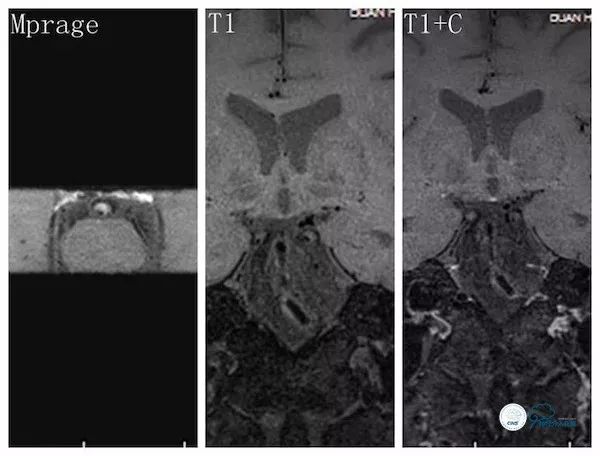

高分辨核磁示(图6):基底动脉斑块形成,横断面可见斑块内出血。

图6

高分辨核磁示(图12):基底动脉多发管壁不均匀偏心性增厚,增强呈局部不均匀强化,Mprage提示斑块内出血。

图12